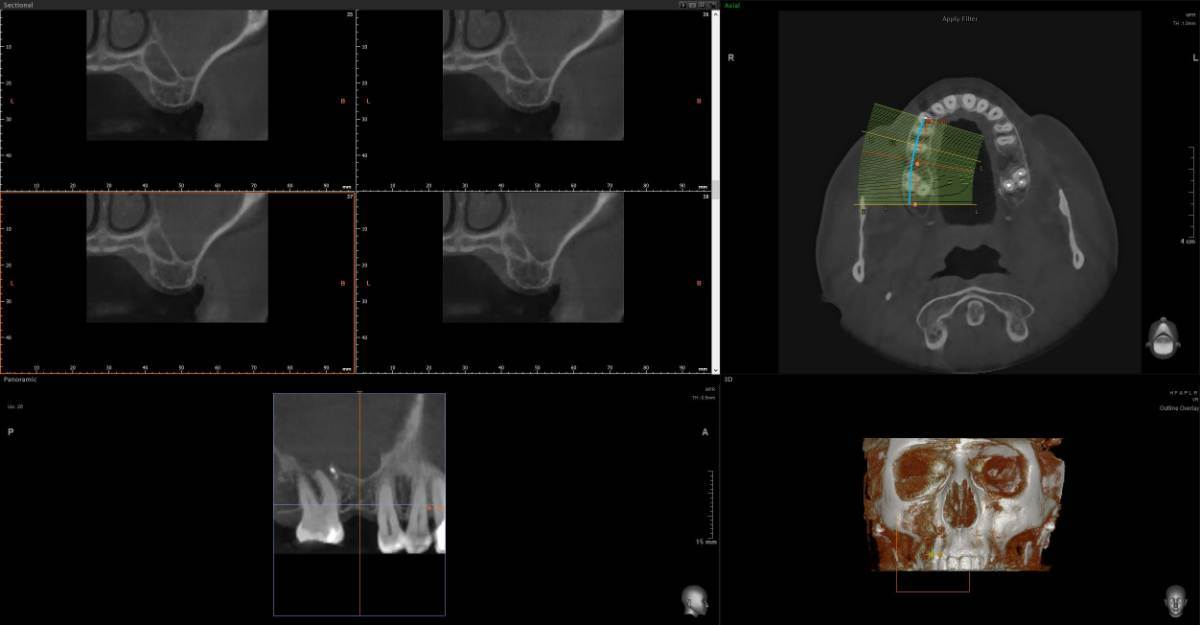

Анна1402 Опубликовано 6 марта Поделиться Опубликовано 6 марта Здравствуйте. Нужно второе мнение. Отправляю два КТ с разницей в три месяца. Первое после удаления. [🗣 «Ситуация такая: 28 ноября отошла коронка, чтобы ее снять, пришлось несколько раз ударять по зубу, решили не распиливать, чтобы сэкономить деньги. По зубу я получила около 30 или более ударов, коронку приклеили обратно, через три дня завоняло тухло. зуб пришлось удалить, была перфорация, перфорацию заложили губками и зашили, через три дня завоняло снова, в процессе этого всего два раза пропивала антибиотики. В конце Декабря хотела сдаться лорам, но так как это было перед праздниками, они меня не взяли, и сказали, что вообще операцию должен вам делать челюстно лицевой хирург, так как у меня дома младенец, я с радостью ушла и решила, буду пока справляться сама, промывала гипертоническим раствором соли, и мне стало лучше, то есть гноя у меня стало меньше, лунка у меня заросла хорошо, показывала челюстно лицевым хирургам, перфорации нет, немного стекает по задней стенке гной, но с каждым днем все меньше и пульсирует левая пазуха, правая, не скажу, что пульсирует, не болит, но были немного выделения, вопрос: на первом Кт, забита одна пазуха, и чем она забита, на втором Кт уже забиты две, хотя чувствую я себя лучше, нос у меня дышит, на первом Кт, когда я делала нос, у меня не дышал, сейчас нос у меня дышит, правая ноздря дышит, ну, вполне нормально, по сравнению с левой. Вот вопрос: делать ли операцию, можно ли ждать, и чем заполнены пазухи: гноем, отек это, или какие то инородные тела? Что это и что вы посоветуете Спойлер Вопрос: почему мне как будто лучше, а на снимке хуже. Что в пазухах? И почему правая стала тоже забита. И сдаться ли 17 марта в больницу к чхл на микрогаморотомию через губу? Заранее очень благодарю за время, которое уделите. Спасибо доктора! https://disk.yandex.ru/d/sTb5_xcHWQVHIw https://disk.yandex.ru/d/1ccGILTzDB1k0g Ссылка на комментарий

Женька Опубликовано 8 марта Поделиться Опубликовано 8 марта @Анна1402 здравствуйте, чем заполнены пазухи по снимкам сказать невозможно. Можно лишь точно сказать, что пазухи тотально затенены (в пазухах что-то есть, гной, кровь, кисты или опухоль). Соустье судя по всему не функционирует. Я бы наоборот через лоров делал. Так как не вижу никаких показаний, идти к ЧЛХ на гайморотомию. Чем делать дырки - лучше эндоскопически зайти в пазуху и санировать. Но перед этим - приём грамотного ЛОР-врача. 1 1 Ссылка на комментарий